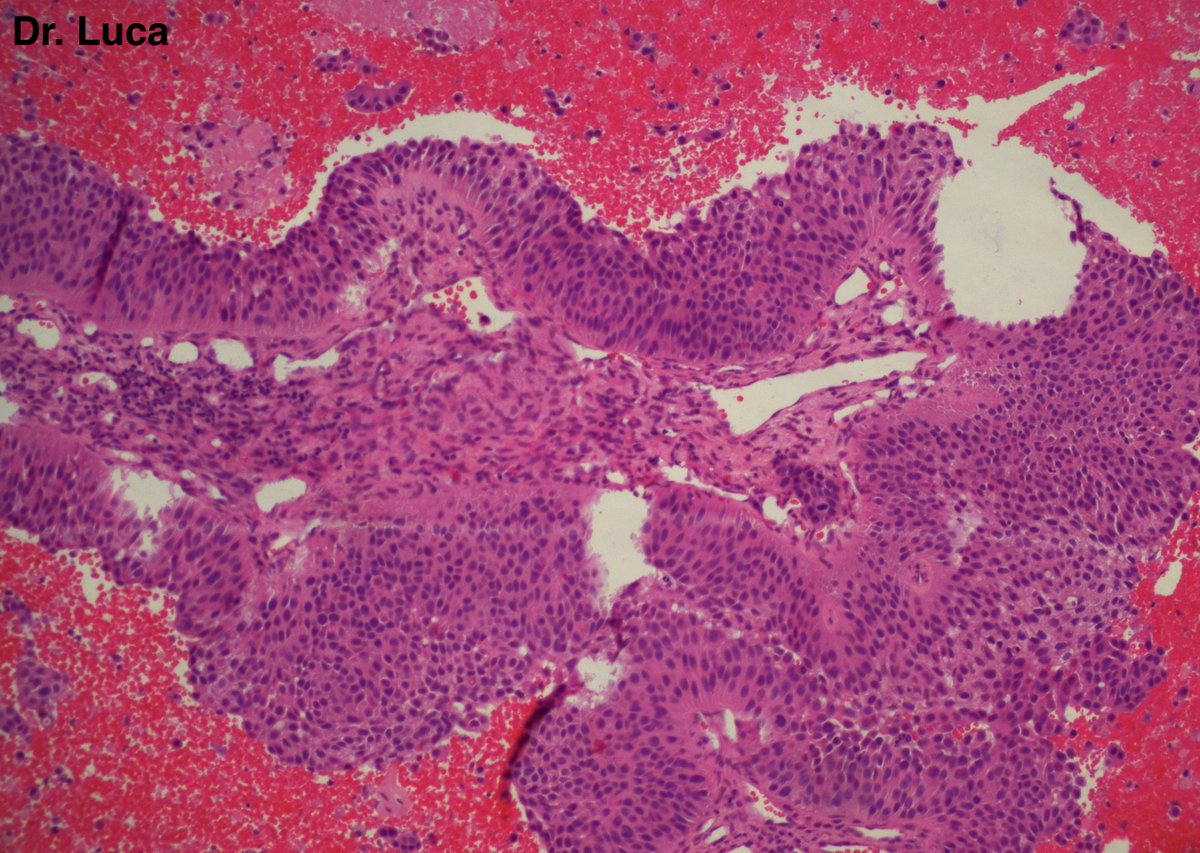

@Pathmath1 @SumantaDas_7 @PoloniaAntonio @ivanaspath @AnapathResident @bansar7 @goziemnweke @Teclis82 @Dr_Brian_Cox @DrBMcGinn @ariella8 @nusrat_xahra @DrRusella_Mirza @glinglerimek @kis_lorand @Venkateshgilly2 @DrBonita16 @DrPayelMondal @DrGeeONE @anjuthevirgo @niki_2389 @pepeheffernan @AngeloCassisa @NeoCrazee @TristanRutland7 Yes, it's a cancer with PNI...I show you the "superficial" layer of this cancer...what is the cancer? and what is the organ? #Pathology #GIpath #PathTwitter #PathResidents #pathboards

2

11